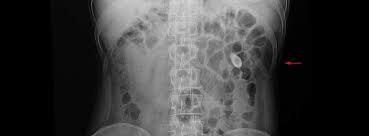

İnsan vücudu, durmaksızın çalışan biyolojik bir fabrikadır. Ancak bazen, böbreklerin o kıvrımlı ve karmaşık tünellerinde işler yolunda gitmez. Tıpkı bir nehrin yatağında biriken tortular gibi, idrarın içindeki mineraller de sessizce çöker. Bu, mikroskobik bir kristalle başlayan, ancak sonunda insanın yaşayabileceği en şiddetli ağrılardan biri olan "Renal Kolik"e dönüşen bir süreçtir.

Yeterince su içilmediğinde veya metabolik bir bozukluk olduğunda, idrar yoğunlaşır. Kalsiyum, okzalat, ürik asit veya fosfat molekülleri birbirine o kadar yakınlaşır ki, "Nükleasyon" başlar.

Olay: İlk kristal oluşur. Bu kristal bir mıknatıs gibi diğerlerini çeker (Agregasyon). Günler, aylar içinde bu mikroskobik yapı büyür, sertleşir ve pürüzlü, keskin bir "taş" halini alır.

Kriz Anı: Bu taş, böbreğin geniş havuzundan (pelvis) çıkıp, idrarı mesaneye taşıyan daracık kanala (üreter) girdiğinde kıyamet kopar. Kanal tıkanır, böbrek şişer ve o meşhur ağrı başlar.